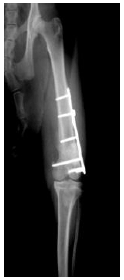

1. ボルゾイの前足の骨折(橈尺骨骨折)

![]() |

ボルゾイという大型犬の前足を横から見たレントゲン写真です。 前足の骨が折れて曲がっています。(白矢印) 骨にヒビが入っている部分もあります。(黄色矢印) |

プレートという器具を使って骨を固定したところです。 骨の折れ方のパターンや、大型犬であることを考慮して、 プレートを2枚使用して治療しています。 |